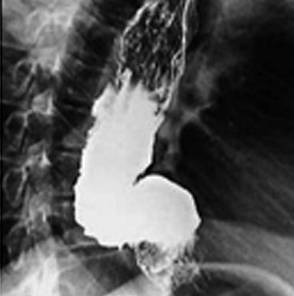

- диагностика при помощи рентген аппарата грудного отдела;

- использование контрастной рентгенографии;